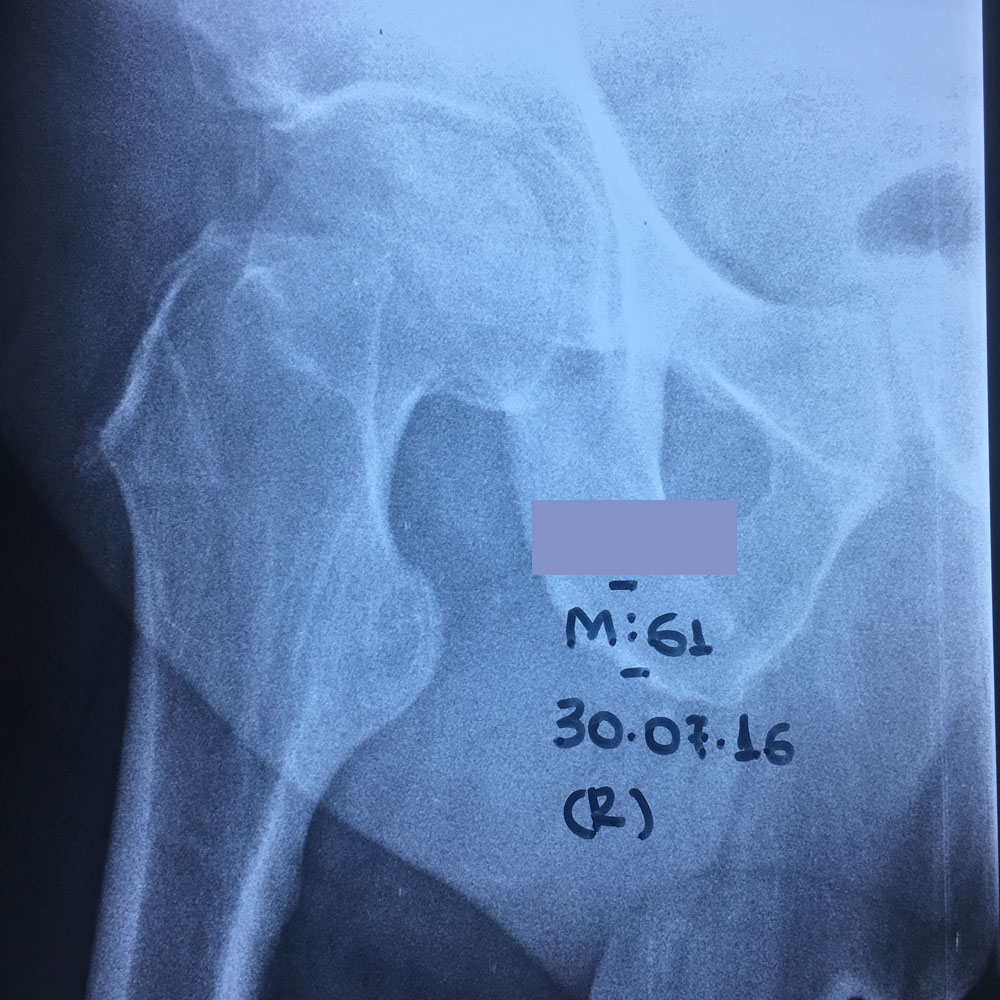

Εικόνα 1(α,β,γ,δ): Οι ακτινογραφίες Face & Profile λεκάνης, ισχίων έδειξαν την ύπαρξη εκφυλιστικών αλλοιώσεων. Ιδιαίτερα στη δεξιά κατ’ ισχίον άρθρωση.

Πρέπει να σημειωθεί ότι οι απλές ακτινογραφίες της λεκάνης-ισχίων σε ουδέτερη θέση και σε απαγωγή, έδειξαν ότι η δεξιά μηριαία κεφαλή απεικονίζεται φυσιολογική με ομαλό περίγραμμα και ήπια σκληρυντική απεικόνιση του υποχονδρίου οστού, ενώ η αριστερή μηριαία κεφαλή ελέγχεται αποπλατυσμένη, ακτινοσκιερή και με ανώμαλο περίγραμμα.